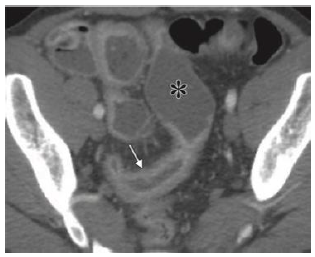

Homem de 29 anos de idade, tabagista, com emagrecimento significativo, dor no quadrante inferior direito do abdome e diarreia recorrentes, admitido no Pronto Atendimento em mal estado geral, 5 evacuações líquidas por dia, febre de 38,2ºC, dor intensa no quadrante inferior direito do abdome, anemia importante, leucocitose, proteína C reativa e calprotectina fecal aumentadas. Além disso, o exame físico revelou lesões compatíveis com eritema nodoso em membros inferiores.

A Figura 1 é representativa dos achados da tomografia computadorizada do abdome realizada na urgência.

Figura 1. Fonte: RadioGraphics 2018; 38:1352–1369

Para este paciente a melhor conduta É: